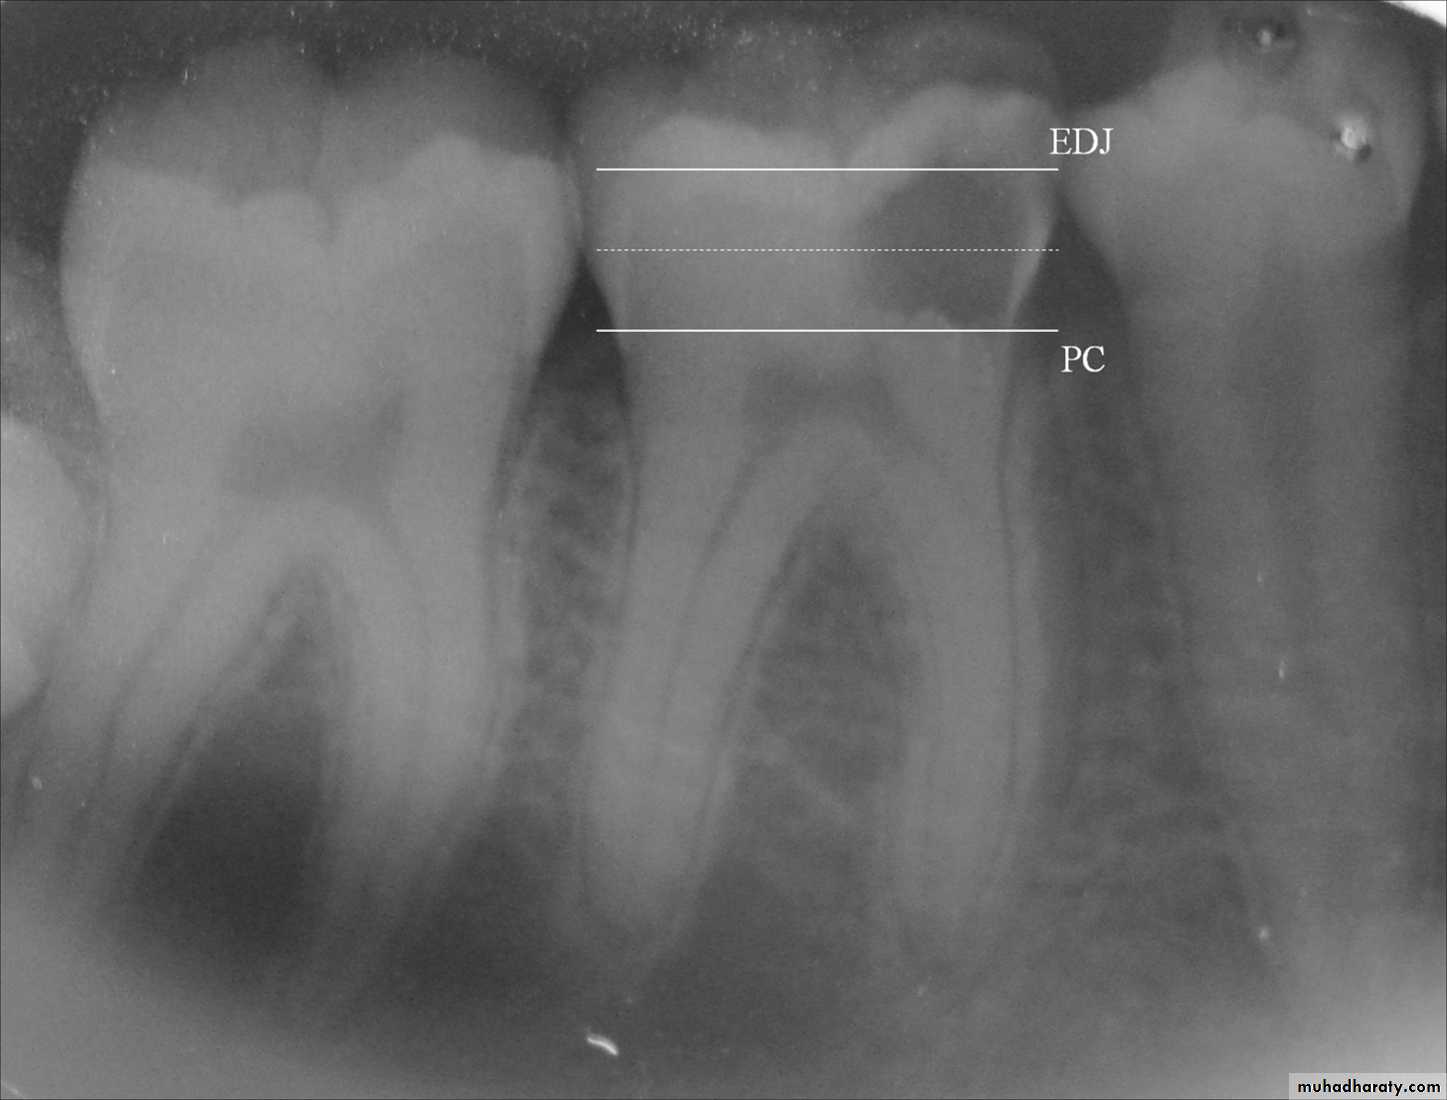

• Deep carious lesion in mandibular molars without pulp involvement.

• A bitewing radiograph of the treated tooth is obtained.

• Remaining dentin thickness(0.5-2mm)• Choice of indirect pulp capping agent.